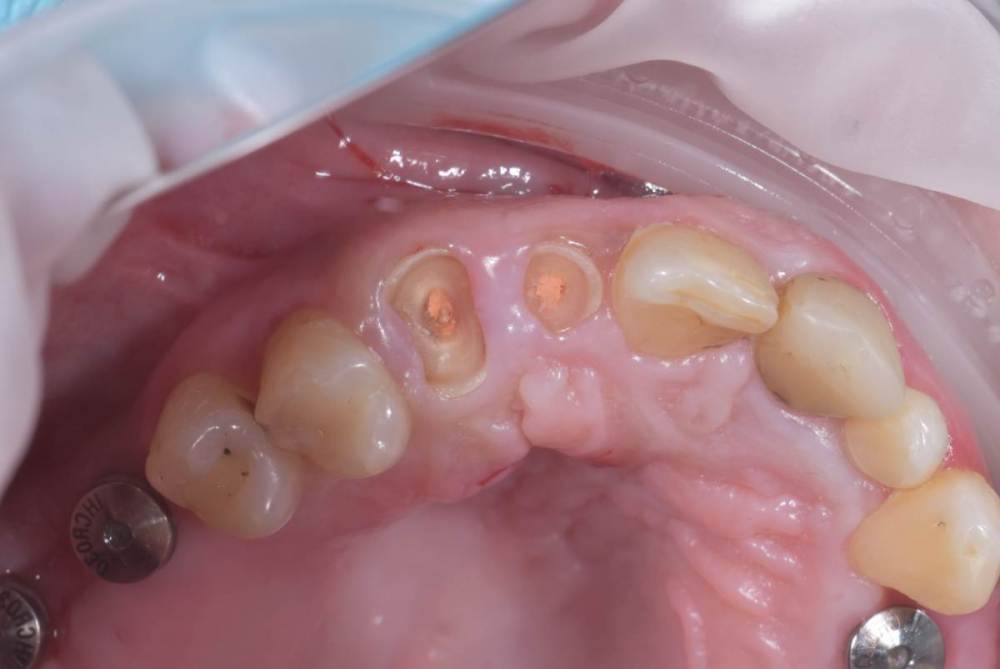

TIGER Опубликовано 3 ноября, 2023 Поделиться Опубликовано 3 ноября, 2023 Периохирургия способна на чудеса)не спешите удалять зубы 5 1 Ссылка на комментарий

АнтонТЛТ Опубликовано 3 ноября, 2023 Поделиться Опубликовано 3 ноября, 2023 Ну раз 12 удлинял, то можно было удлинить с аркой зенита и сделать как 22 Ссылка на комментарий

TIGER Опубликовано 3 ноября, 2023 Автор Поделиться Опубликовано 3 ноября, 2023 @АнтонТЛТ Антон честно,лень было)Пациентка довольна как слон,эстетические требования приемлимые.Поэтому не стал навязывать доп манипуляцию.Поэтому тут считаю результат приемлимый Ссылка на комментарий